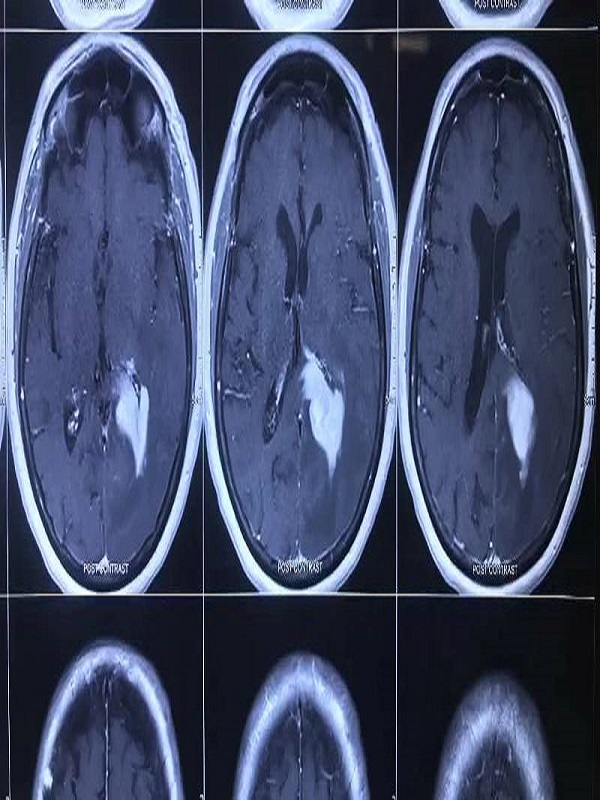

Brain Surgery

Brain Surgery refers to various medical procedures that involve repairing structural problems in the brain. There are numerous types of brain surgery. The type used is based on the area of the brain and the condition being treated

Brain Stroke & Paralysis

A stroke is a condition that is typically referred to as a cardiovascular accident or a CVA. Symptoms of stroke include trouble walking, speaking and understanding, as well as paralysis or numbness of the face, arm or leg.

Brain Tumor

A brain tumor is a mass or growth of abnormal cells in your brain. Many different types of brain tumors exist. Some brain tumors are noncancerous (benign), and some brain tumors are cancerous (malignant).